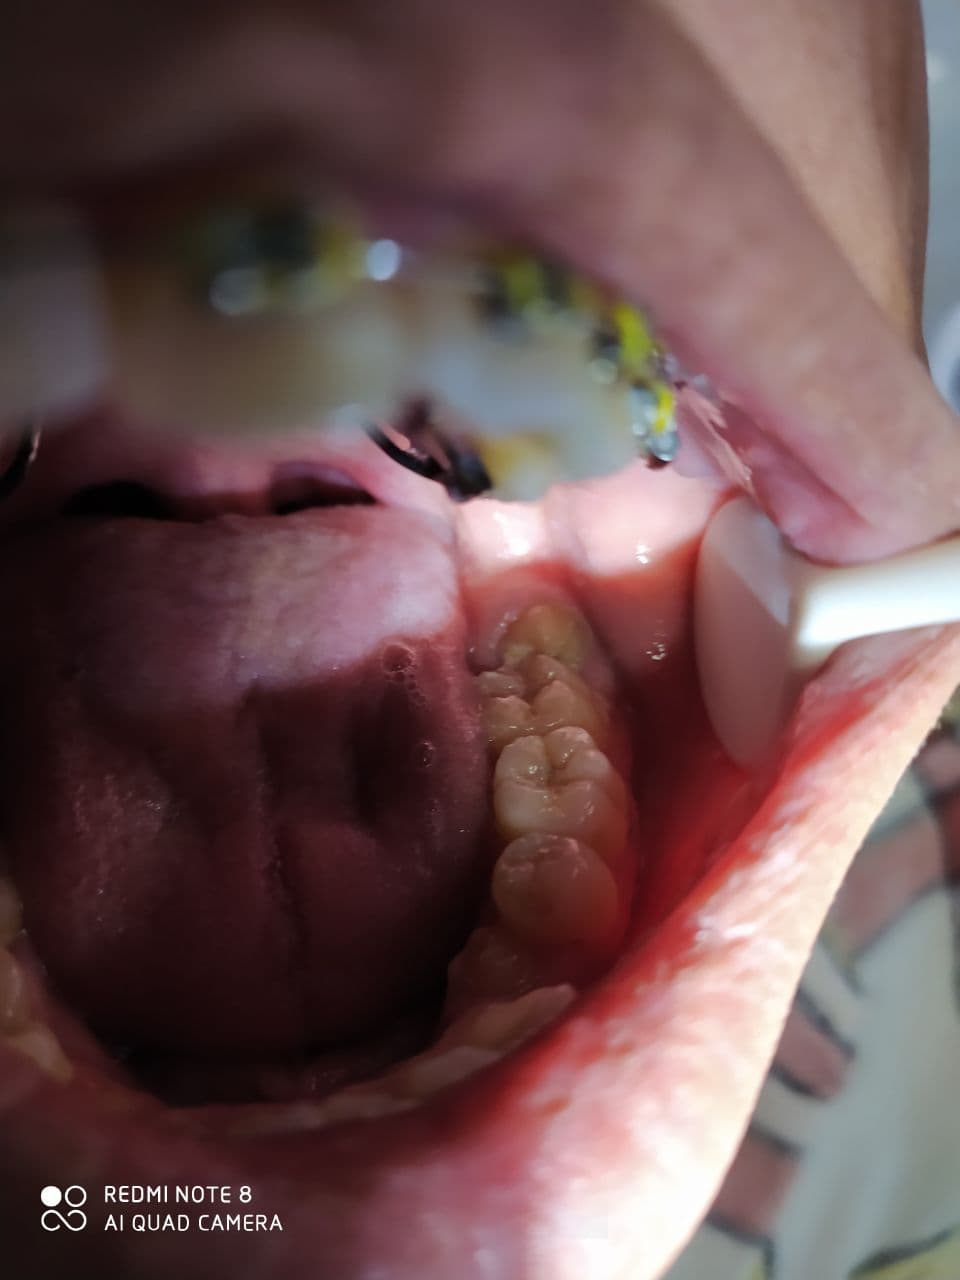

تميز وابداع الطالبه تبارك أحمد في أجراء عملية قلع سن العقل

بأشراف الدكتور سمير سعد الجشعمي اجرت الطالبة في قسم طب الأسنان المرحله الخامسة تبارك احمد جبار عملية قلع سن عقل مطمور حيث كان يعاني المريض من ألم شديد في سن العقل مما تطلب أجراء عملية جراحيه له وقلعه . يذكر أن عملية قلع سن العقل من العمليات الصعبه التي تحتاج التي خبره ومهاره كافيه لاجرائها وهذا ما اظهرته الطالبه تبارك من خلال عملها المتميز في عيادات قسم طب الأسنان وكذلك امتلاكها الخبره والمهاره الكافيه المكتسبه من العمل الحثيث و المتواصل.